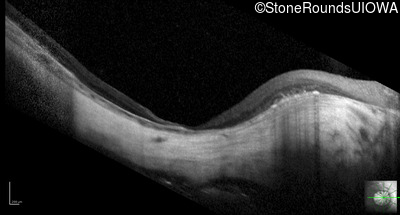

Optical Coherence Tomography - Left - 20/100

Exemplar / OCT Stack

OCT Stack